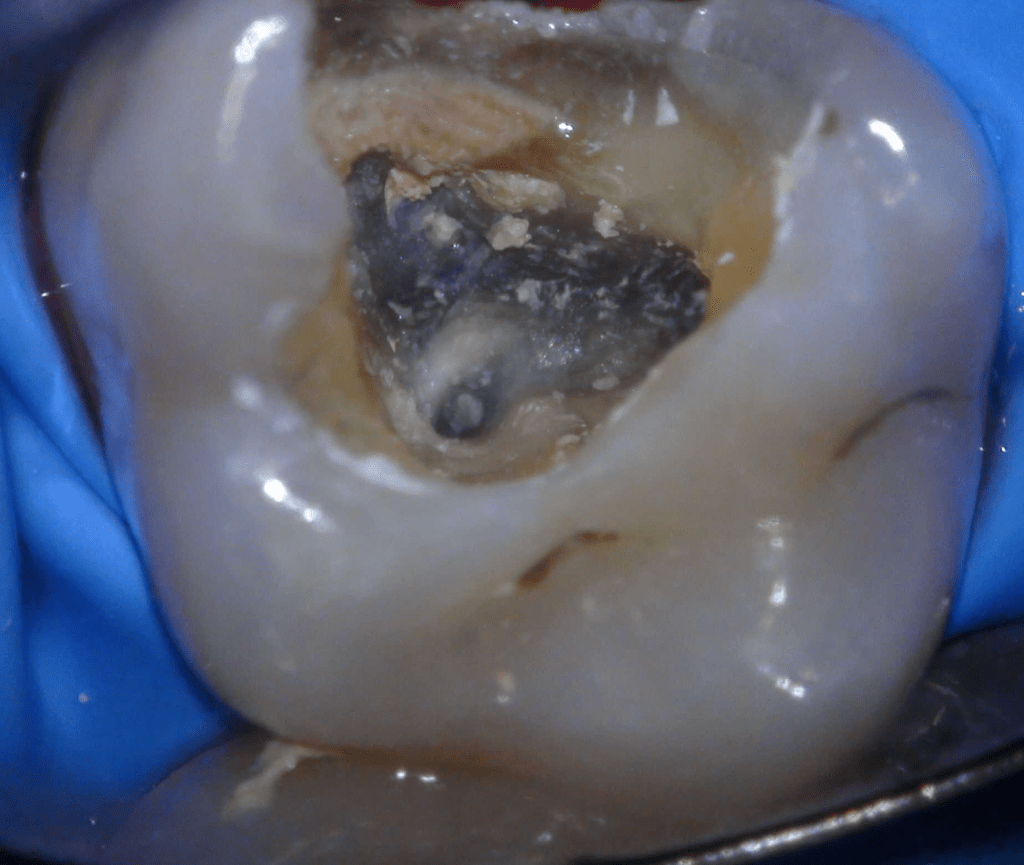

Fisura, remoción amalgama para explorar